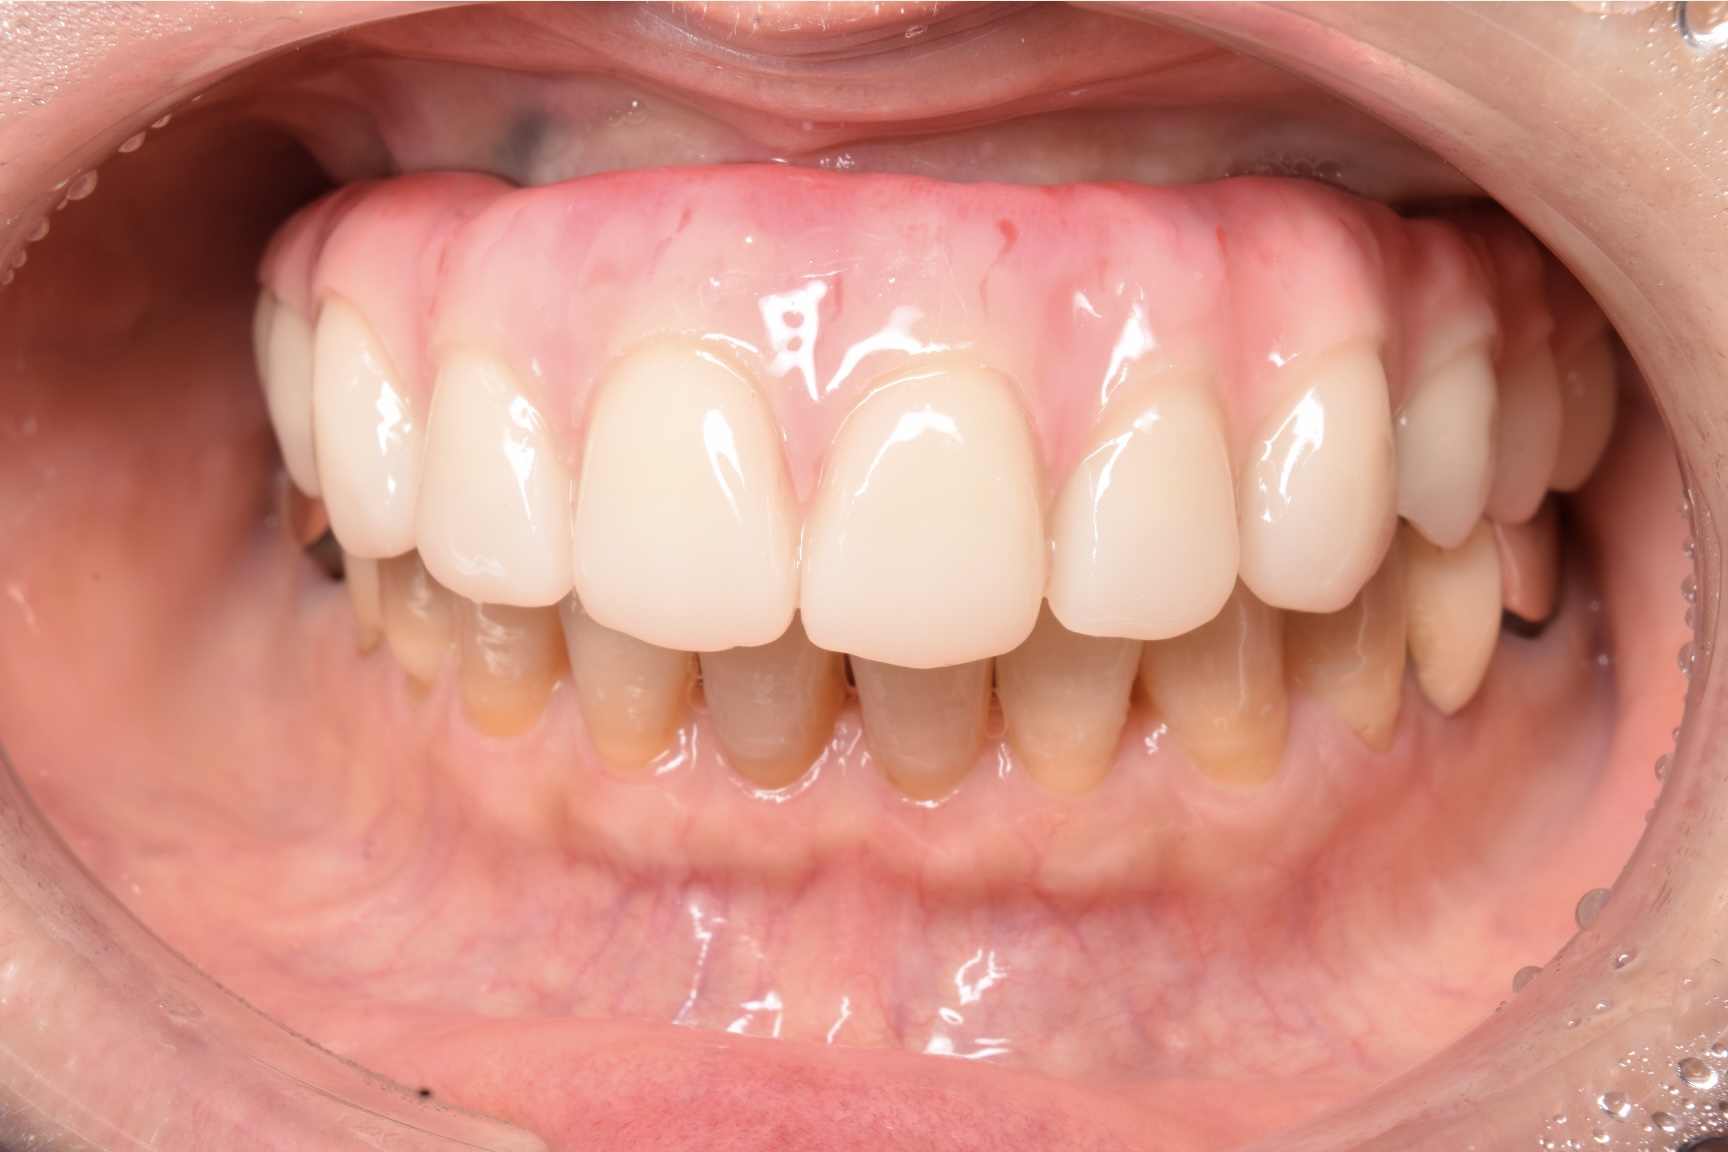

CASE

治療を終えて